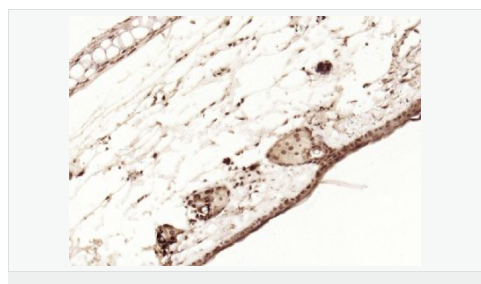

| 產(chǎn)品應(yīng)用 | WB=1:1000-2000 ELISA=1:1000-5000 IHC-P=1:100-500 IHC-F=1:100-500 Flow-Cyt=1ug/Test ICC=1:100-500 IF=1:100-500 (石蠟切片需做抗原修復) not yet tested in other applications. optimal dilutions/concentrations should be determined by the end user. |